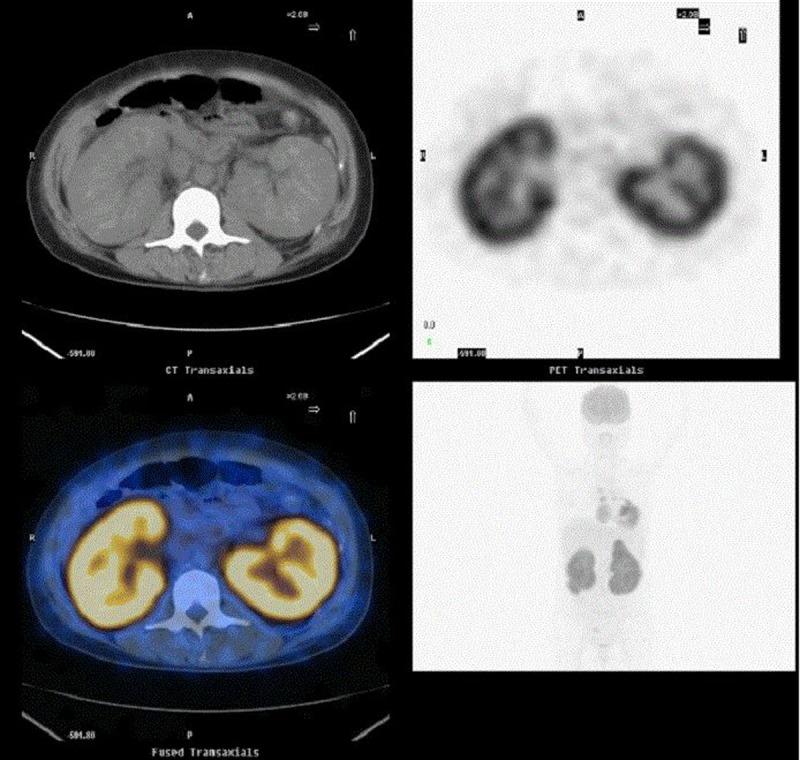

In this study we describe a 27-year-old Chinese woman with central nervous system leukemia due to PRL. It was classified as diffuse large B-cell lymphoma non-GCB type according to kidney biopsy. We selected R-CHOP as a regimen and it showed good curative effect. However, the patient suffered recurrence involving the central nervous system with complaint of intolerable iliac-sacral pain at 26 days after 6 courses of R-CHOP.

在本研究中,我们描述了一名27岁的中国女性,因原发性肾淋巴瘤导致中枢神经系统白血病。根据肾活检,其被分类为非生发中心B细胞型弥漫性大B细胞淋巴瘤。我们选择R-CHOP方案,显示出良好的疗效。然而,该患者在接受6个疗程的R-CHOP治疗后26天复发,累及中枢神经系统,主诉骶髂部疼痛难忍。